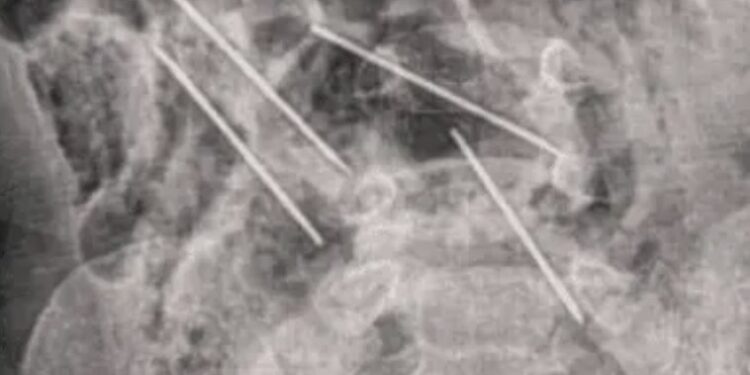

Al llegar al hospital la madre informó de lo sucedido a los médicos y éstos intervinieron rápido para ayudarlo, donde lo primero que hicieron fue sacarle una radiografía para determinar dónde estaban las agujas.

Luego de la radiografía los médicos notaron que algunas de estas agujas se encontraban muy cerca de los órganos vitales del bebé, por lo que tuvieron que someterlo a cirugía casi de forma inmediata debido al riesgo que estas representaban.